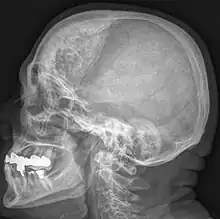

Hyperostosis frontalis interna is a common, benign thickening of the inner side of the frontal bone of the skull. It is found predominantly in women after menopause and is usually asymptomatic. Mostly frequently it is found as an incidental finding discovered during an X-ray or CT scan of the skull.

Hyperostosis frontalis at CT